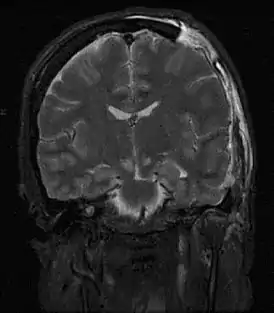

![]() МРТ, показывающая дислокацию мозга | |